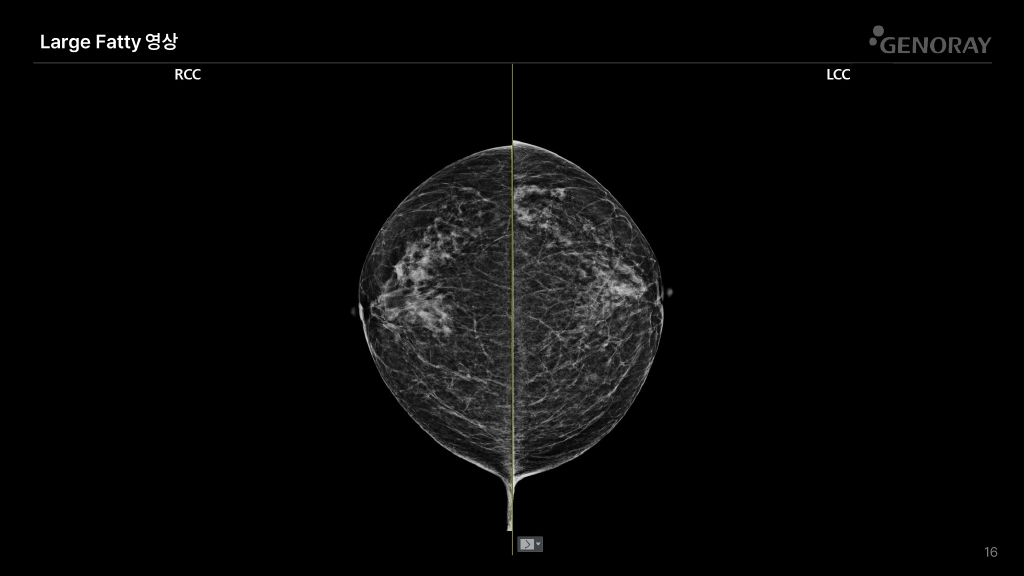

CLINICAL IMAGES

오랜 경험을 통해 축적된 노하우로 진단영상을 제공합니다.